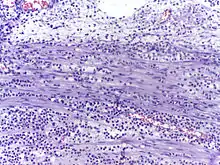

In autopsy, the presence of neutrophils in the heart or brain is one of the first signs of infarction, and is useful in the timing and diagnosis of myocardial infarction and stroke.

- Neutrophils are seen in a myocardial infarction at approximately 12–24 hours,[61] as seen in this micrograph.